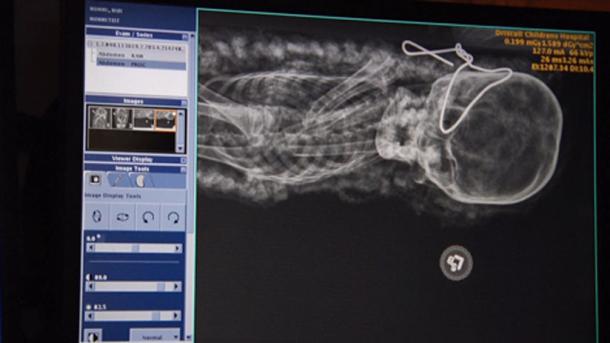

2,000-year-old mummy taken to Driscoll Children's Hospital for X-rays (Youtube Screenshot)

Driscoll Children’s Hospital X-ray of the mummy confirms age, gender and even cause of death (Corpus Christi Museum of Natural History and Science)

The Xray revealed the girl’s legs were tucked in to her body, making the mummy appear small (Youtube Screenshot)